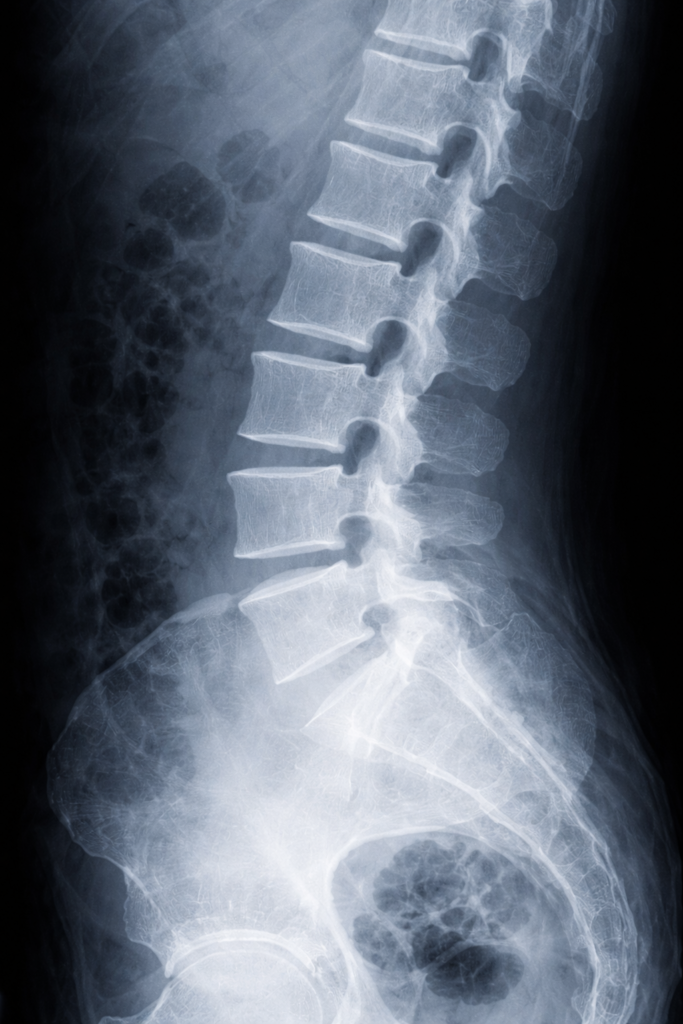

腰椎圧迫骨折とは

腰椎圧迫骨折とは、背骨のうち腰の部分に圧力がかかり、潰れた状態になった骨折です。

日常生活では転倒などにより生じる可能性があり、交通事故でも腰に強い衝撃が加わることで生じるケースがあります。加齢により骨粗しょう症になっていると、軽い力が加わっただけで骨折するケースも少なくありません。

腰椎圧迫骨折のケガを負うと、腰に強い痛みが生じるほか、下半身のしびれが生じる場合もあります。

治療法としては、コルセットで固定する保存療法が基本ですが、重度だと手術も考えられます。

いずれにしても回復までは相当の時間を要し、後遺症が残るケースもある重大なケガです。